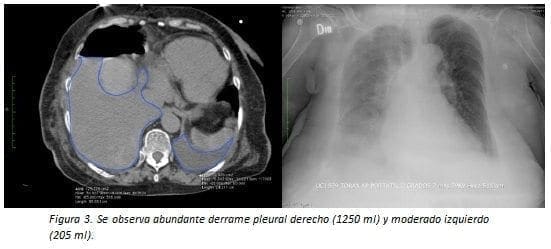

La cantidad depende del área en cm2 obtenida en escanografía de tórax en corte axial en el sitio donde era más abundante. Esta medida del área fue convertida en mililitros utilizando la fórmula ml = (cm2 x 100) x 0,1.

A su vez fue determinado como escaso si es <75 ml, moderado entre 75 y 350 ml y abundante si es mayor de 350 ml (figuras 1-5).